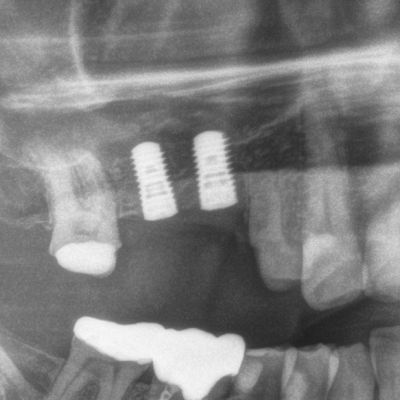

Sinuslift mit Eigenknochen und späterer Implantation

Implantation & Sinuslift (Aufbau des Kieferknochens in der Kieferhöhle)